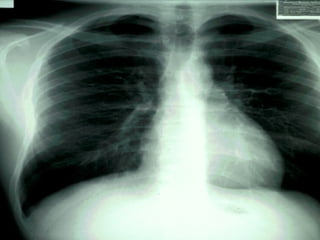

Outside air between the pleural membranes  (pneumothorax) allows the elastic lung to collapse inward and the chest wall to expand outward.  The pleural cavity becomes obvious.  Once the lung is collapsed, the person has only the one lung to survive on.

Figure 25.07c

Outside air betweenthe pleural membranes (pneumothorax) allows the elastic lung to collapse inward and the chest wall to expand outward. The pleural cavity becomes obvious. Once the lung is collapsed, the person has only the one lung to survive on.